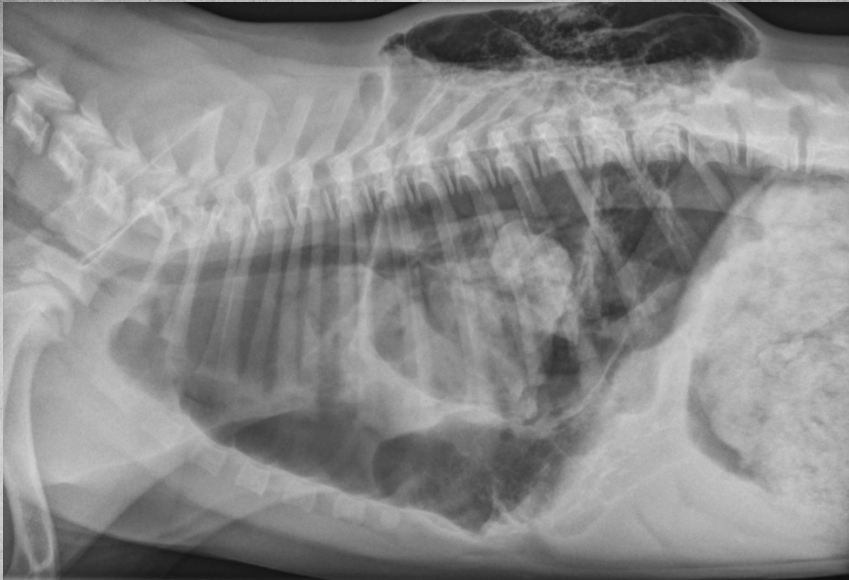

● 2 yo Labrador

● Ingested laundry detergent the day

before

black hole is bifurcation

air bronchograms visible -> alveolar pattern

lobar sign in lower VD image

aspiration pneumonia -> chemical burn in the lungs secondary to laundry detergent aspiration